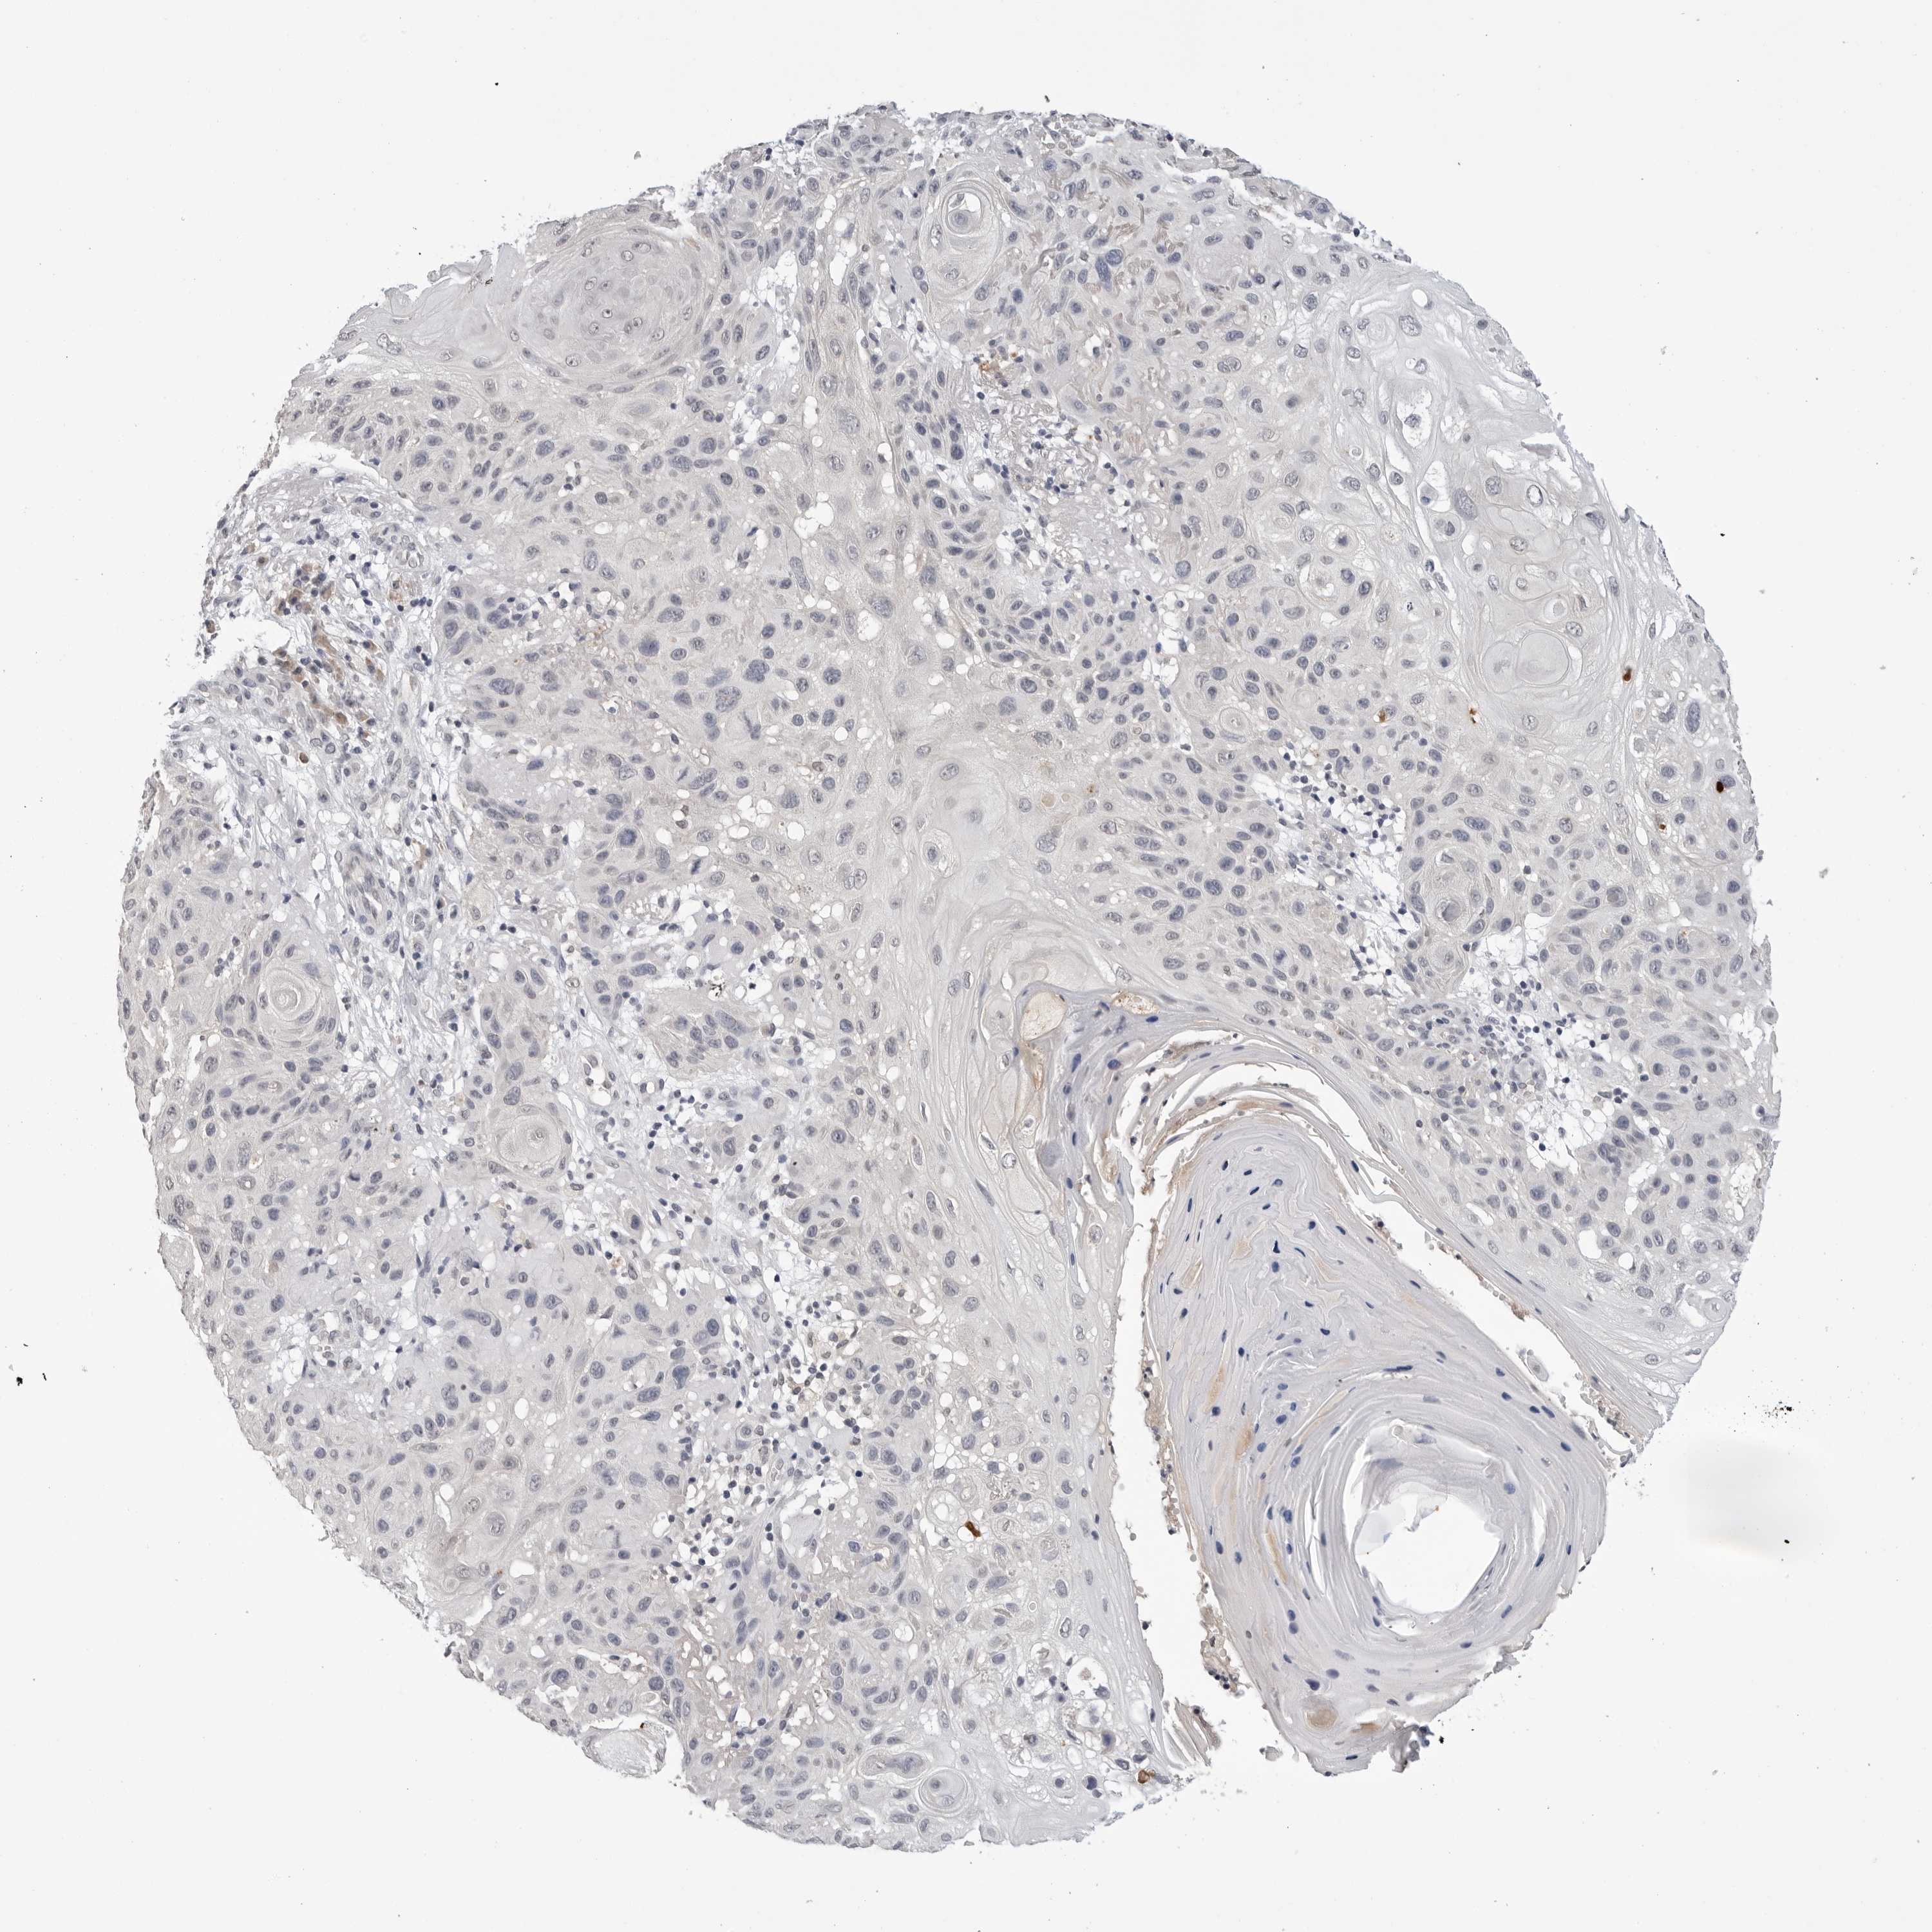

Basal cell and squamous cell cancer

SKIN CANCER - Protein expressioni

A mouse-over function shows sample information and annotation data. Click on an image to view it in a full screen mode. Samples can be filtered based on level of antibody staining by selecting one or several of the following categories: high, medium, low and not detected. The assay and annotation is described here.

Each image is clickable and will lead to virtual microscopy that enables deeper exploration of all samples and also displays staining intensity scores, fraction scores and subcellular localization as well as patient and tissue information for each sample.

Antibody HPA027379

Squamous cell carcinoma, NOS